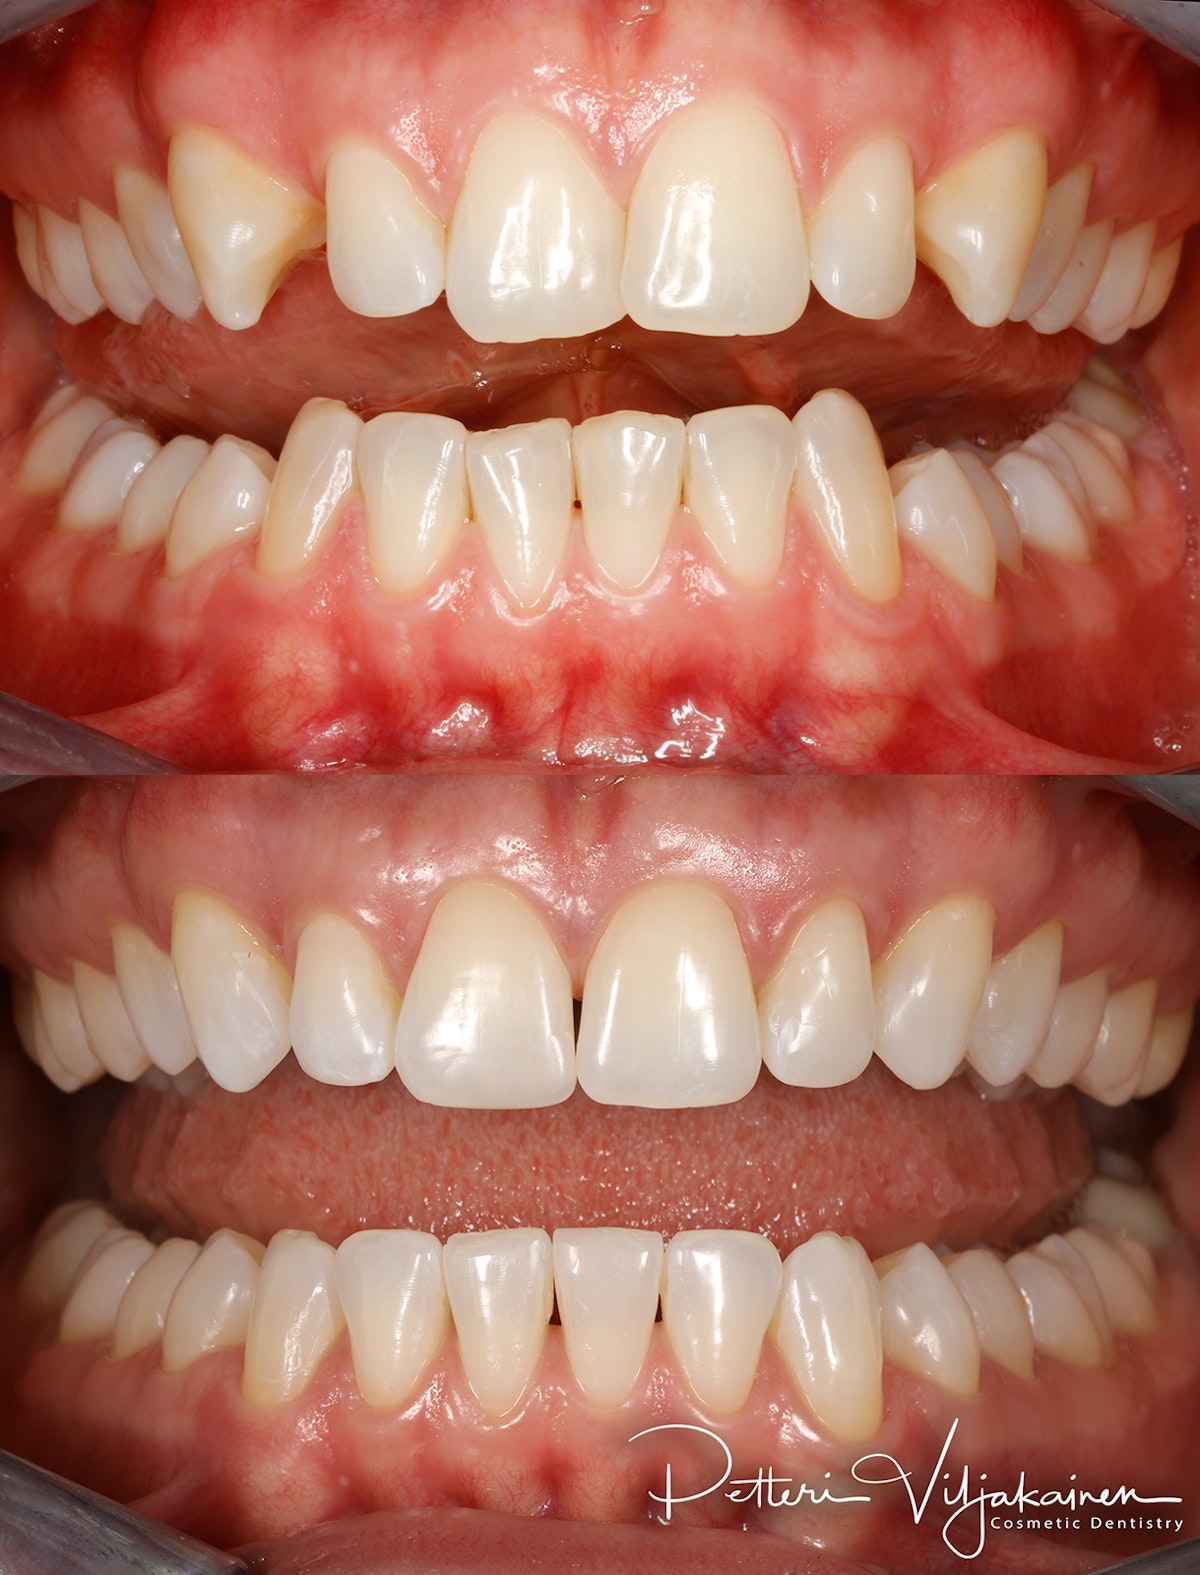

20kk hoito (Comprehensive).